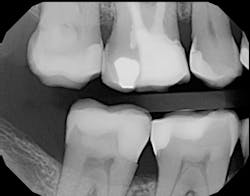

Figure 1 shows a large radiolucency on the mesial and a small radiolucency on the occlusal of tooth 31. Figure 2 shows an initial caries lesion on the distal pit and a leaking occlusal composite. Tooth 31 was sensitive to cold but normal to chewing, bite, and heat. Selective caries removal was used to prevent pulp exposure and preserve the marginal ridge.